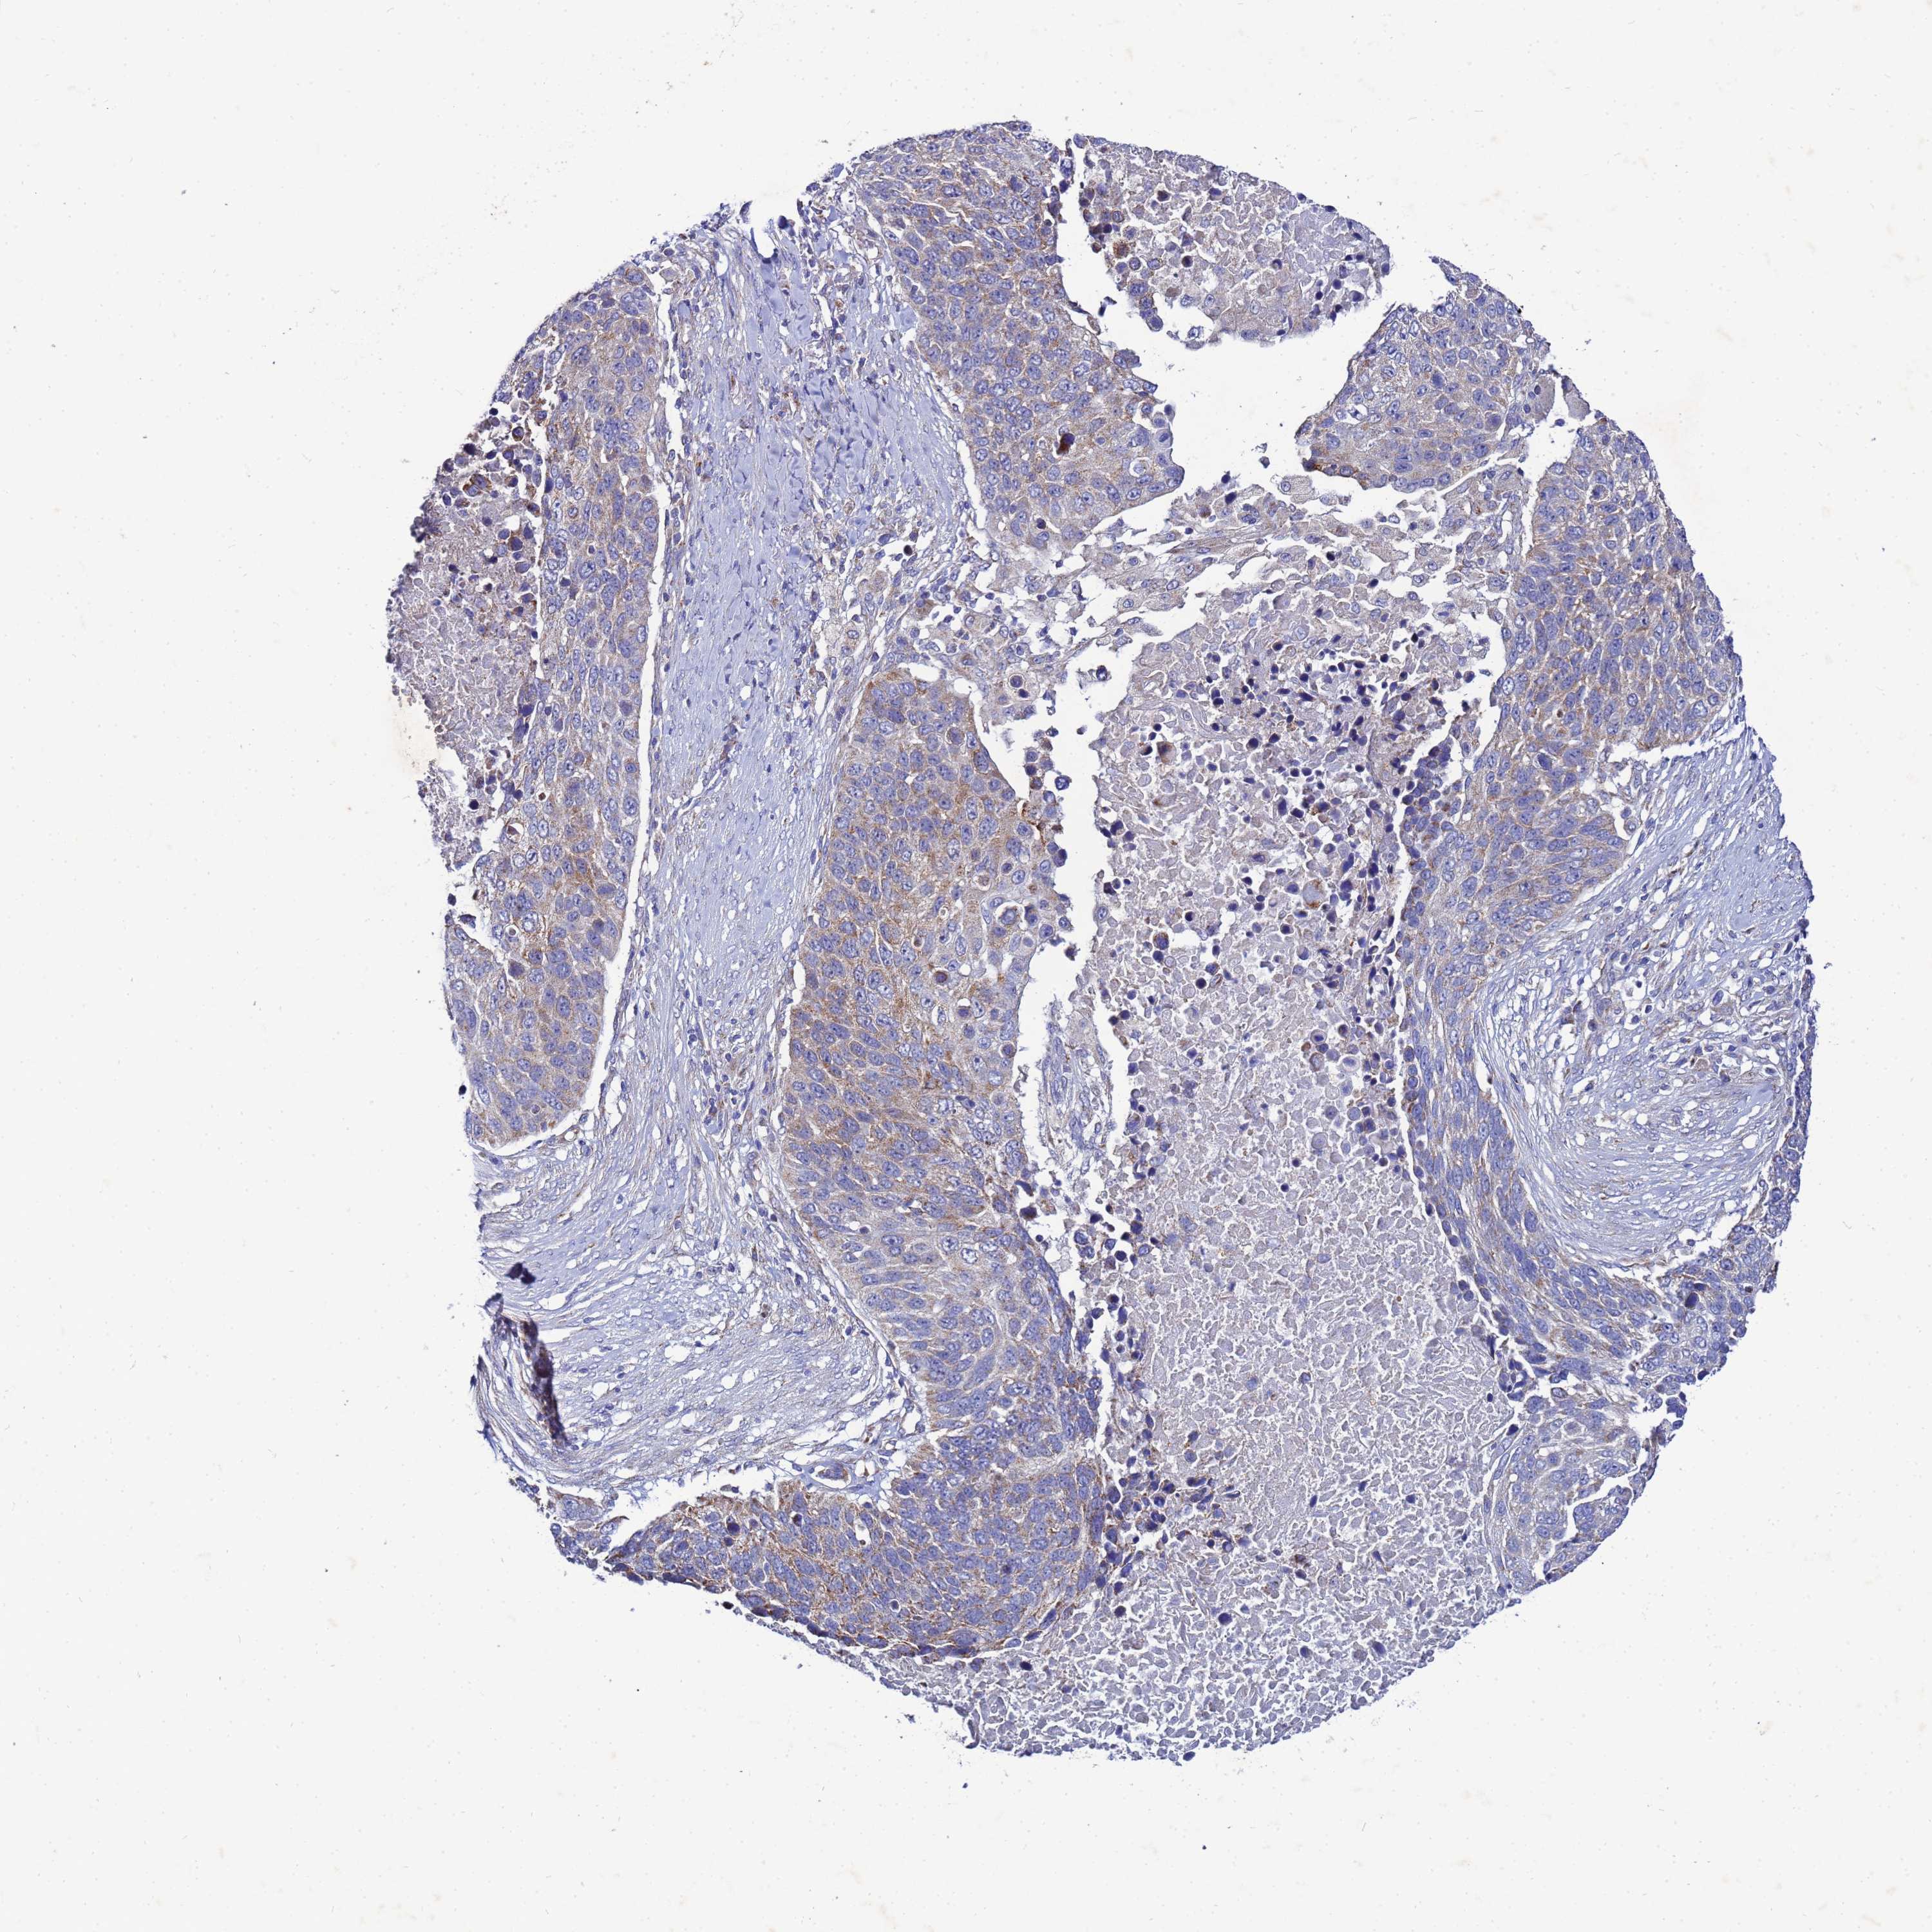

LUNG SQUAMOUS CELL CARCINOMA (TCGA) - Interactive survival scatter ploti

The Survival Scatter plot shows the clinical status (i.e. dead or alive) for all individuals in the patient cohort, based on the same data that underlies the corresponding Kaplan-Meier plots. Patients that are alive at last time for follow-up are shown in blue and patients who have died during the study are shown in red.

The x-axis shows the expression levels (FPKM) of the investigated gene in the tumor tissue at the time of diagnosis. The y-axis shows the follow-up time after diagnosis (years). Both axes are complimented with kernel density curves demonstrating the data density over the axes. The top density plot shows the expression levels (FPKM) distribution among dead (red) and alive patients (blue). The right density plot shows the data density of the survived years of dead patients with high and low expression levels respectively, stratified using the cutoff indicated by the vertical dashed line through the Survival Scatter plot. This cutoff is automatically defined based on the FPKM cutoff that minimizes the p-score. The cutoff can be changed by dragging the vertical line or by entering a cutoff value in the square labeled "Current cut-off".

Under the Survival Scatter plot the p-score landscape (black curve; left axis) is shown together with dead median separation (red curve; right axis). Dead median separation is the difference in median mRNA expression between patients who have died with high and low expression, respectively. It is calculated as follows: median FPKM expression of dead patients with high expression - median FPKM expression of dead patients with low expression. This is intended to aid the user in visually exploring custom cutoffs and the associated p-scores and dead median separation.

Individual patient data is displayed and can be filtered by clicking on one or more of the category buttons on the top of the page. Categories describing expression level and patient information include: high, low, alive, dead, female, male and tumor stages. The scale of the x-axis can be toggled between linear and log-scale by clicking on the "x log" button. Mouse-over function shows TCGA ID, patient information and mRNA expression (FPKM) for each patient.

& Survival analysisi

Kaplan-Meier plots summarize results from analysis of correlation between mRNA expression level and patient survival. Patients were divided based on level of expression into one of the two groups "low" (under cut off) or "high" (over cut off). X-axis shows time for survival (years) and y-axis shows the probability of survival, where 1.0 corresponds to 100 percent.

FAHD2A is not prognostic in Lung Squamous Cell Carcinoma (TCGA)

: 19.75

P scorei

N/A

Average pTPM 21.3

Number of samples 489